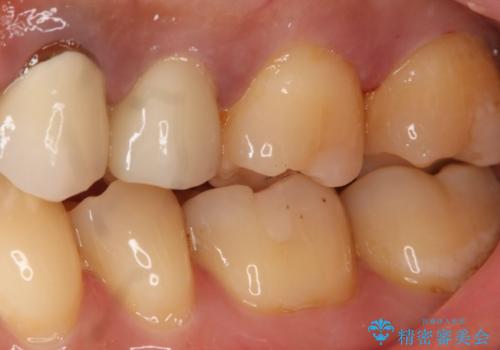

- 左上7番の銀歯のやり変えを希望された患者様です。

セラミックでの治療を希望されたため切削量などを考慮し、セラミックインレーでの治療を計画しました。

銀歯を除去し形態を整えたのち、印象しています。